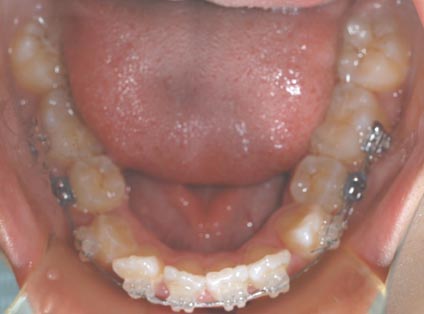

1.叢生(乱ぐい歯) 歯が重なり合ってでこぼこしています

治療前

上顎両側4番を抜歯

下顎両側4番も抜歯